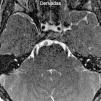

Se solicitó una resonancia magnética (RM) de ambas órbitas con cortes finos en el tronco encefálico, focalizados en la cisterna prepontina, sin gadolinio. En las órbitas no se encontraron alteraciones (no se muestra la imagen), mientras que a nivel de la cisterna pontina en secuencias balanced fast field echo(BFFE) y en ponderación T2 drive tridimensional (3D) con reconstrucción multiplanar se objetivó la ausencia del sexto nervio craneal izquierdo (fig. 1).

Una correcta anamnesis, exploración clínica y estudios por imágenes como la RM permiten arribar al diagnóstico correcto3,4. La no visualización del sexto par en la RM confirma el diagnóstico de SRD, especialmente con secuencias ponderadas en T2 y 3D2–4,7. El contraste endovenoso (gadolinio) no es de utilidad.